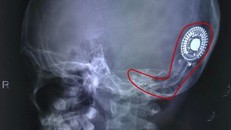

[Ngày Nay] - Khoảng 90% trẻ em câm điếc có cha mẹ là những người có khả năng nghe bình thường. Cấy ốc tai là một lựa chọn đầy hấp dẫn đối với họ bởi nó hứa hẹn sẽ giúp cha mẹ và con có thể giao tiếp với nhau dễ dàng hơn.